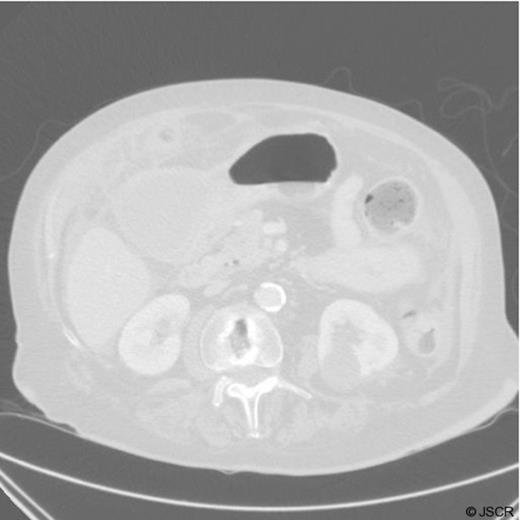

A CT scan of the abdomen and pelvis was requested which revealed inflammation surrounding the anterior of the stomach, a large irregular thick-walled collection arising from the fundus of the gallbladder, free fluid around the liver, spleen and paracolic gutter. Appearances were consistent with gallbladder perforation.

CT Scan demonstrating a thick walled gallbladder with free fluid in the paracolic gutter and a collection in the porta hepatis

It is unclear from the CT images whether the cyst is contained within the gastric cavity. Malignancy was also a potential concern at this stage.